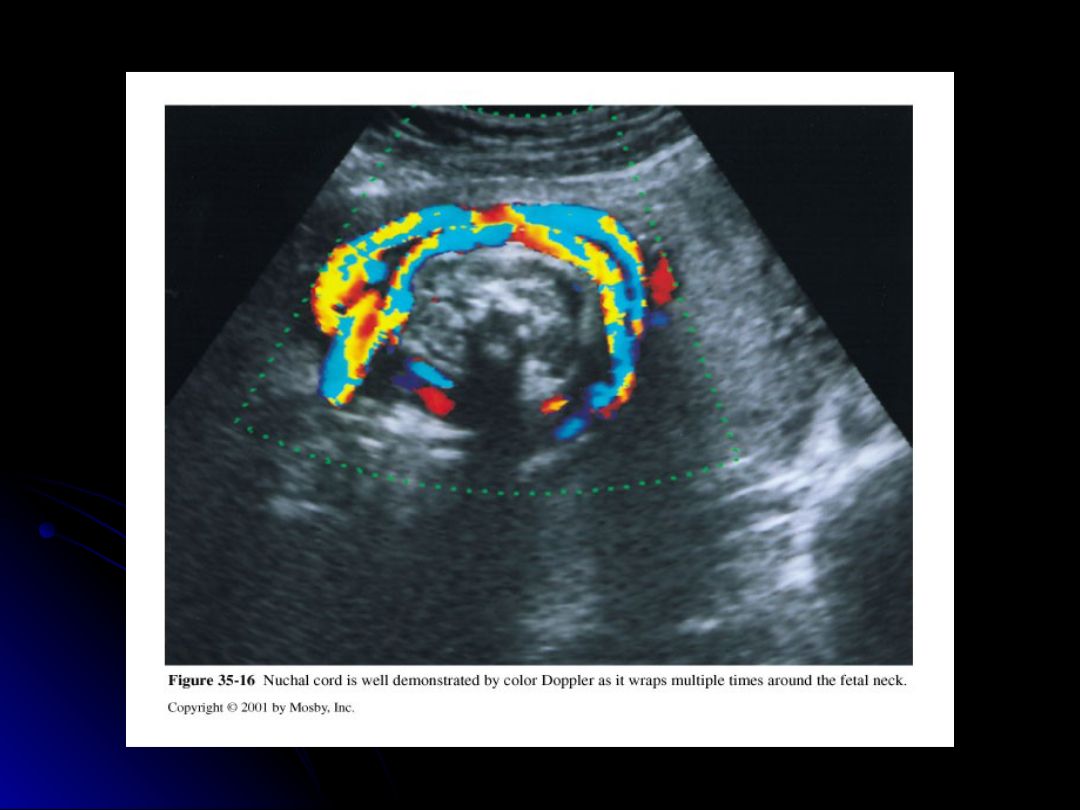

Which one of the following umbilical cord entanglements in the fetus is the most common?

nuchal cord